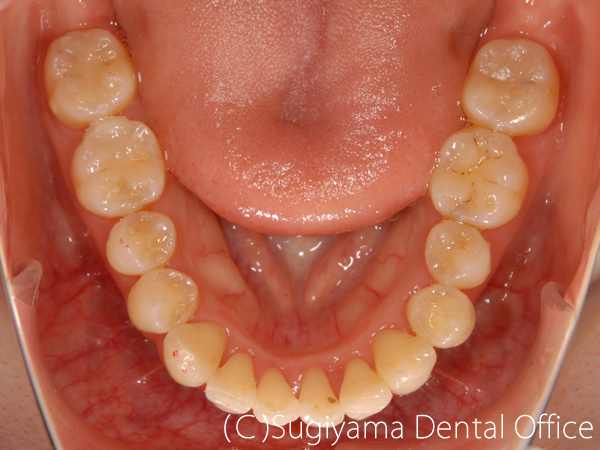

10歳の女性です。 術前写真を見ると、上の前歯2本が内側に傾斜していることがわかります(丸印)。 このような歯の傾斜によって下のあごの位置が奥に押し込まれ顎関節症になる方が少なくありません。

術後1年後には綺麗な歯並びになっただけでなく、機能的なあごの運動ができるようになりました。